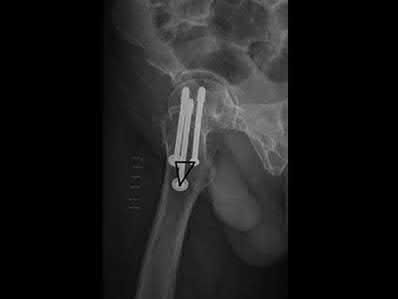

Which of the following is a recognized predictor of mortality after hip fracture?

American Society of Anesthesiologist (ASA) classification is predictive of post-surgical mortality in hip fracture patients.

The ASA classification (detailed in Illustration A) was initially developed in 1963 and has been shown to be predictive of post-surgical mortality in hip fracture patients. Basic categories are as follows: 1= normal, healthy; 2= mild systemic disease; 3= severe systemic disease, not incapacitating; 4= severe incapacitating systemic condition, constant threat to life; 5= moribund patient; 6 = brain dead, organs being donated.

Richmond et al. looked at 836 patients treated for a hip fracture and found that this injury is not associated with significant excess mortality among patients older than age 85. However, in younger patients, those with ASA classifications of 3 or 4 have significant excess mortality following hip fracture that persists up to 2 years after injury.

Holt et al. investigated the relationship between a number of patient and management variables and mortality after surgery for fracture of the hip. Data relating to 18,817 patients were obtained from the Scottish Hip Fracture Audit database. They found that type of anesthetic did not adversely affect the 30 or 120 day mortality rate.